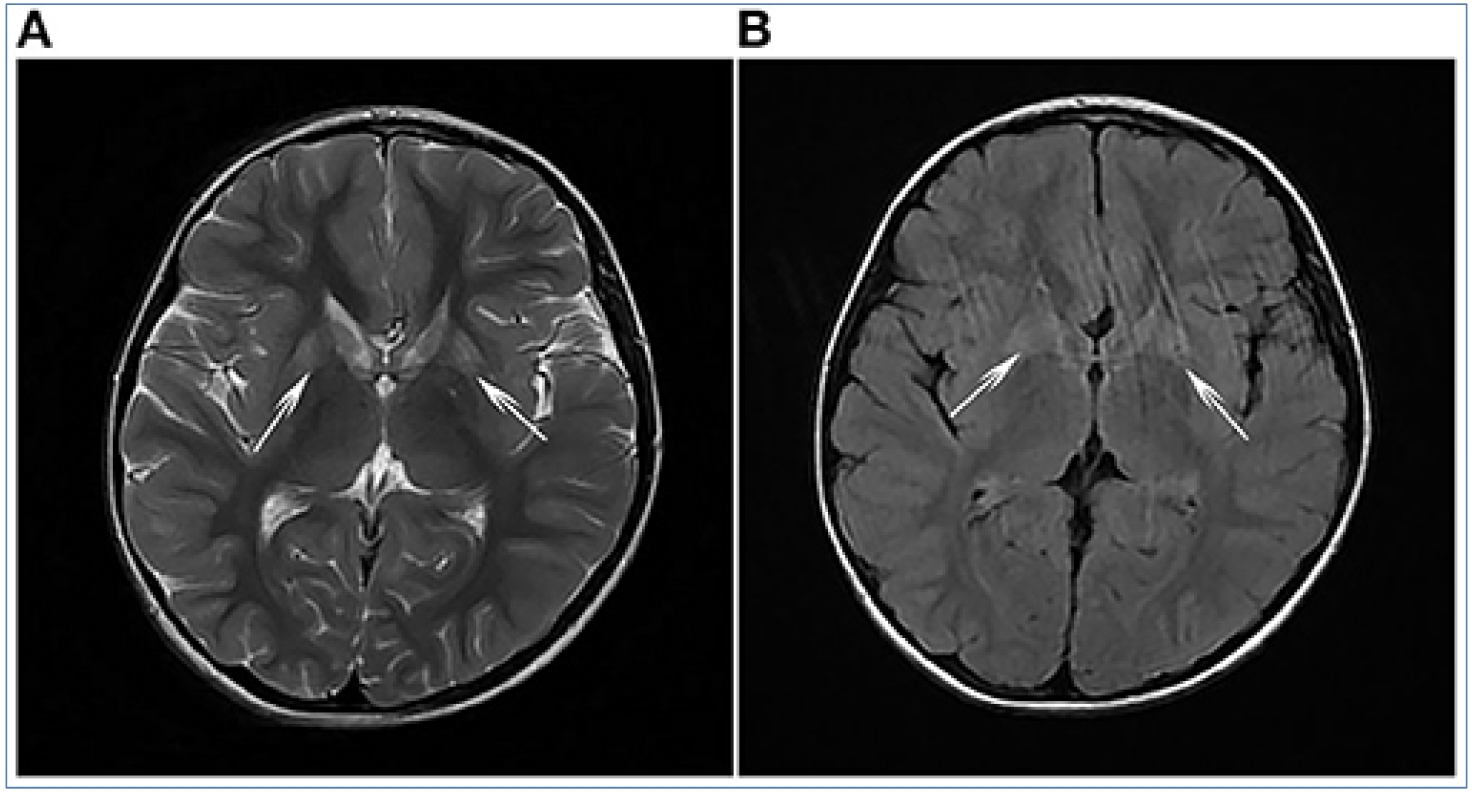

FIGURE 1. (A) T2-weighted imaging (T2WI) and (B) fluid-attenuated inversion recovery (FLAIR) analyses revealed symmetrical flake abnormal signal shadows in bilateral basal ganglia (white arrows).

该报告提到含丝氨酸活性位点的蛋白1(serine active site-containing protein 1:SERAC1)双等位基因变异通常会导致MEGDEL综合征,其临床特征是尿液中3-甲基戊烯二酸的排泄增加、肌肉张力减退、感音神经性耳聋和脑MRI扫描上的Leigh样病变。本报告介绍了一个中国家庭的病例,该家庭因SERAC1变异而出现代谢紊乱和肌张力障碍;先证者的临床表型与MEGDEL综合征不同,但与青少年发病的遗传性痉挛性截瘫相似。因此这项研究旨在确认SERAC1变异与复杂的遗传性痉挛性截瘫之间的关系。方法采用对先证者进行MRI和实验室检查,包括气相色谱/质谱(GC/MS)代谢筛查用于检测尿液中3-甲基戊烯二酸。全外显子组测序用于检测候选SERAC1突变。使用Sanger测序验证了突变个体。使用各种软件程序(PolyPhen-2、MutationTaster、PROVEAN和SIFT)预测新突变的致病性。结果发现脑MRI扫描显示,双侧基底节出现对称片状异常信号阴影,GC/MS分析中发现3-甲基戊二酸的排泄量增加。全外显子组测序显示了新的复合杂合突变,包括从父亲遗传的SERAC1外显子14中的新c.1495A>G(p.Met499Val)突变和从母亲遗传的外显子8中的新c.721_722delAG(p.Leu242fs)突变。致病性预测结果表明,这两种变异是有害的。因此通过本研究介绍了一名由SERAC1变异引起的复杂遗传性痉挛性截瘫患者。这些发现扩大了已知SERAC1变异的数量以及与SERAC1缺乏相关的表型谱。这项研究可能有助于通过产前咨询和预防遗传性疾病。